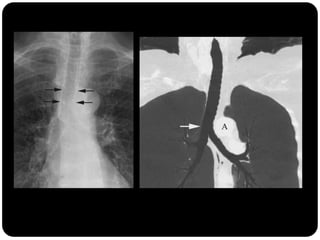

Traquéia       Linha paratraqueal direita (interface do LSD

Brônquios       com parede lateral direita da traquéia): não

Bronquíolos     deve ultrapassar 4mm ;

 Parede paratraqueal esquerda circundada por

tecido adiposo e vasos mediastinais 

normalmente não é vista na radiografia;

O que está anormal?